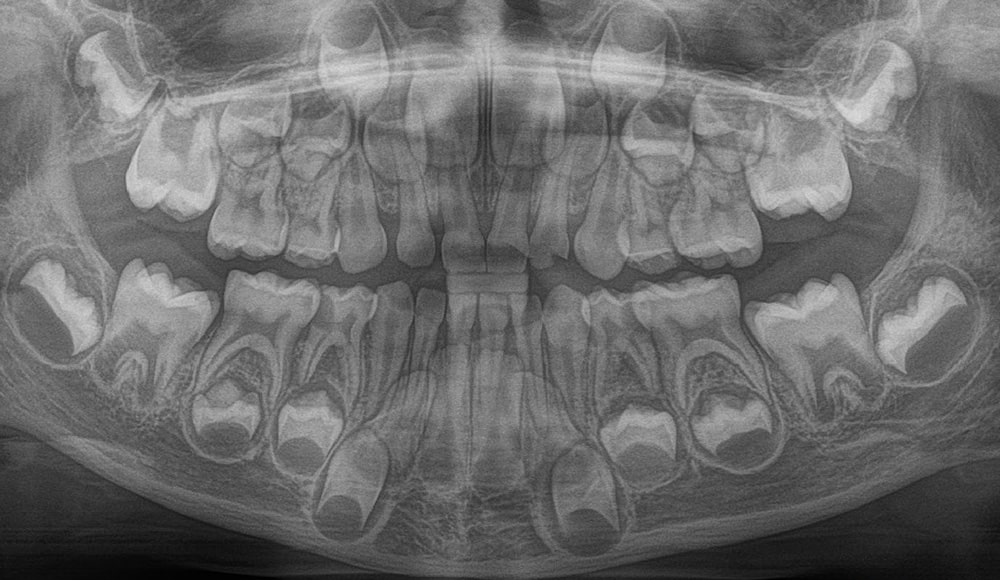

Children usually begin to get their baby teeth within the first 6 months of life. By around 6 to 7 years, they start losing these primary teeth, which are gradually replaced by permanent teeth. Between 6 and 12 years, children have a mixed dentition - a combination of baby and permanent teeth.

Although milk teeth eventually fall out, decay or damage in them should never be ignored. Untreated infections can spread and affect the developing permanent teeth inside the bone. It’s also important to retain the primary molars (back teeth) until around 10–12 years of age, as they help guide the proper eruption and alignment of permanent teeth.